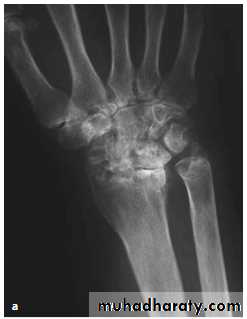

Radiological evaluation

Upper limbs